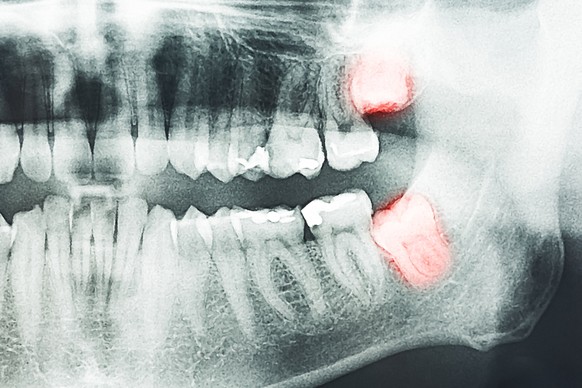

Les dents de sagesse

Indispensables autrefois pour mâcher des végétaux fibreux ou de la viande crue, les dents de sagesse sont devenues superflues au vu de notre alimentation plus tendre et transformée. La mâchoire humaine s'étant également rétrécie, la pousse des dents de sagesse provoque souvent douleurs et inflammations. Beaucoup de personnes ne les développent déjà plus.